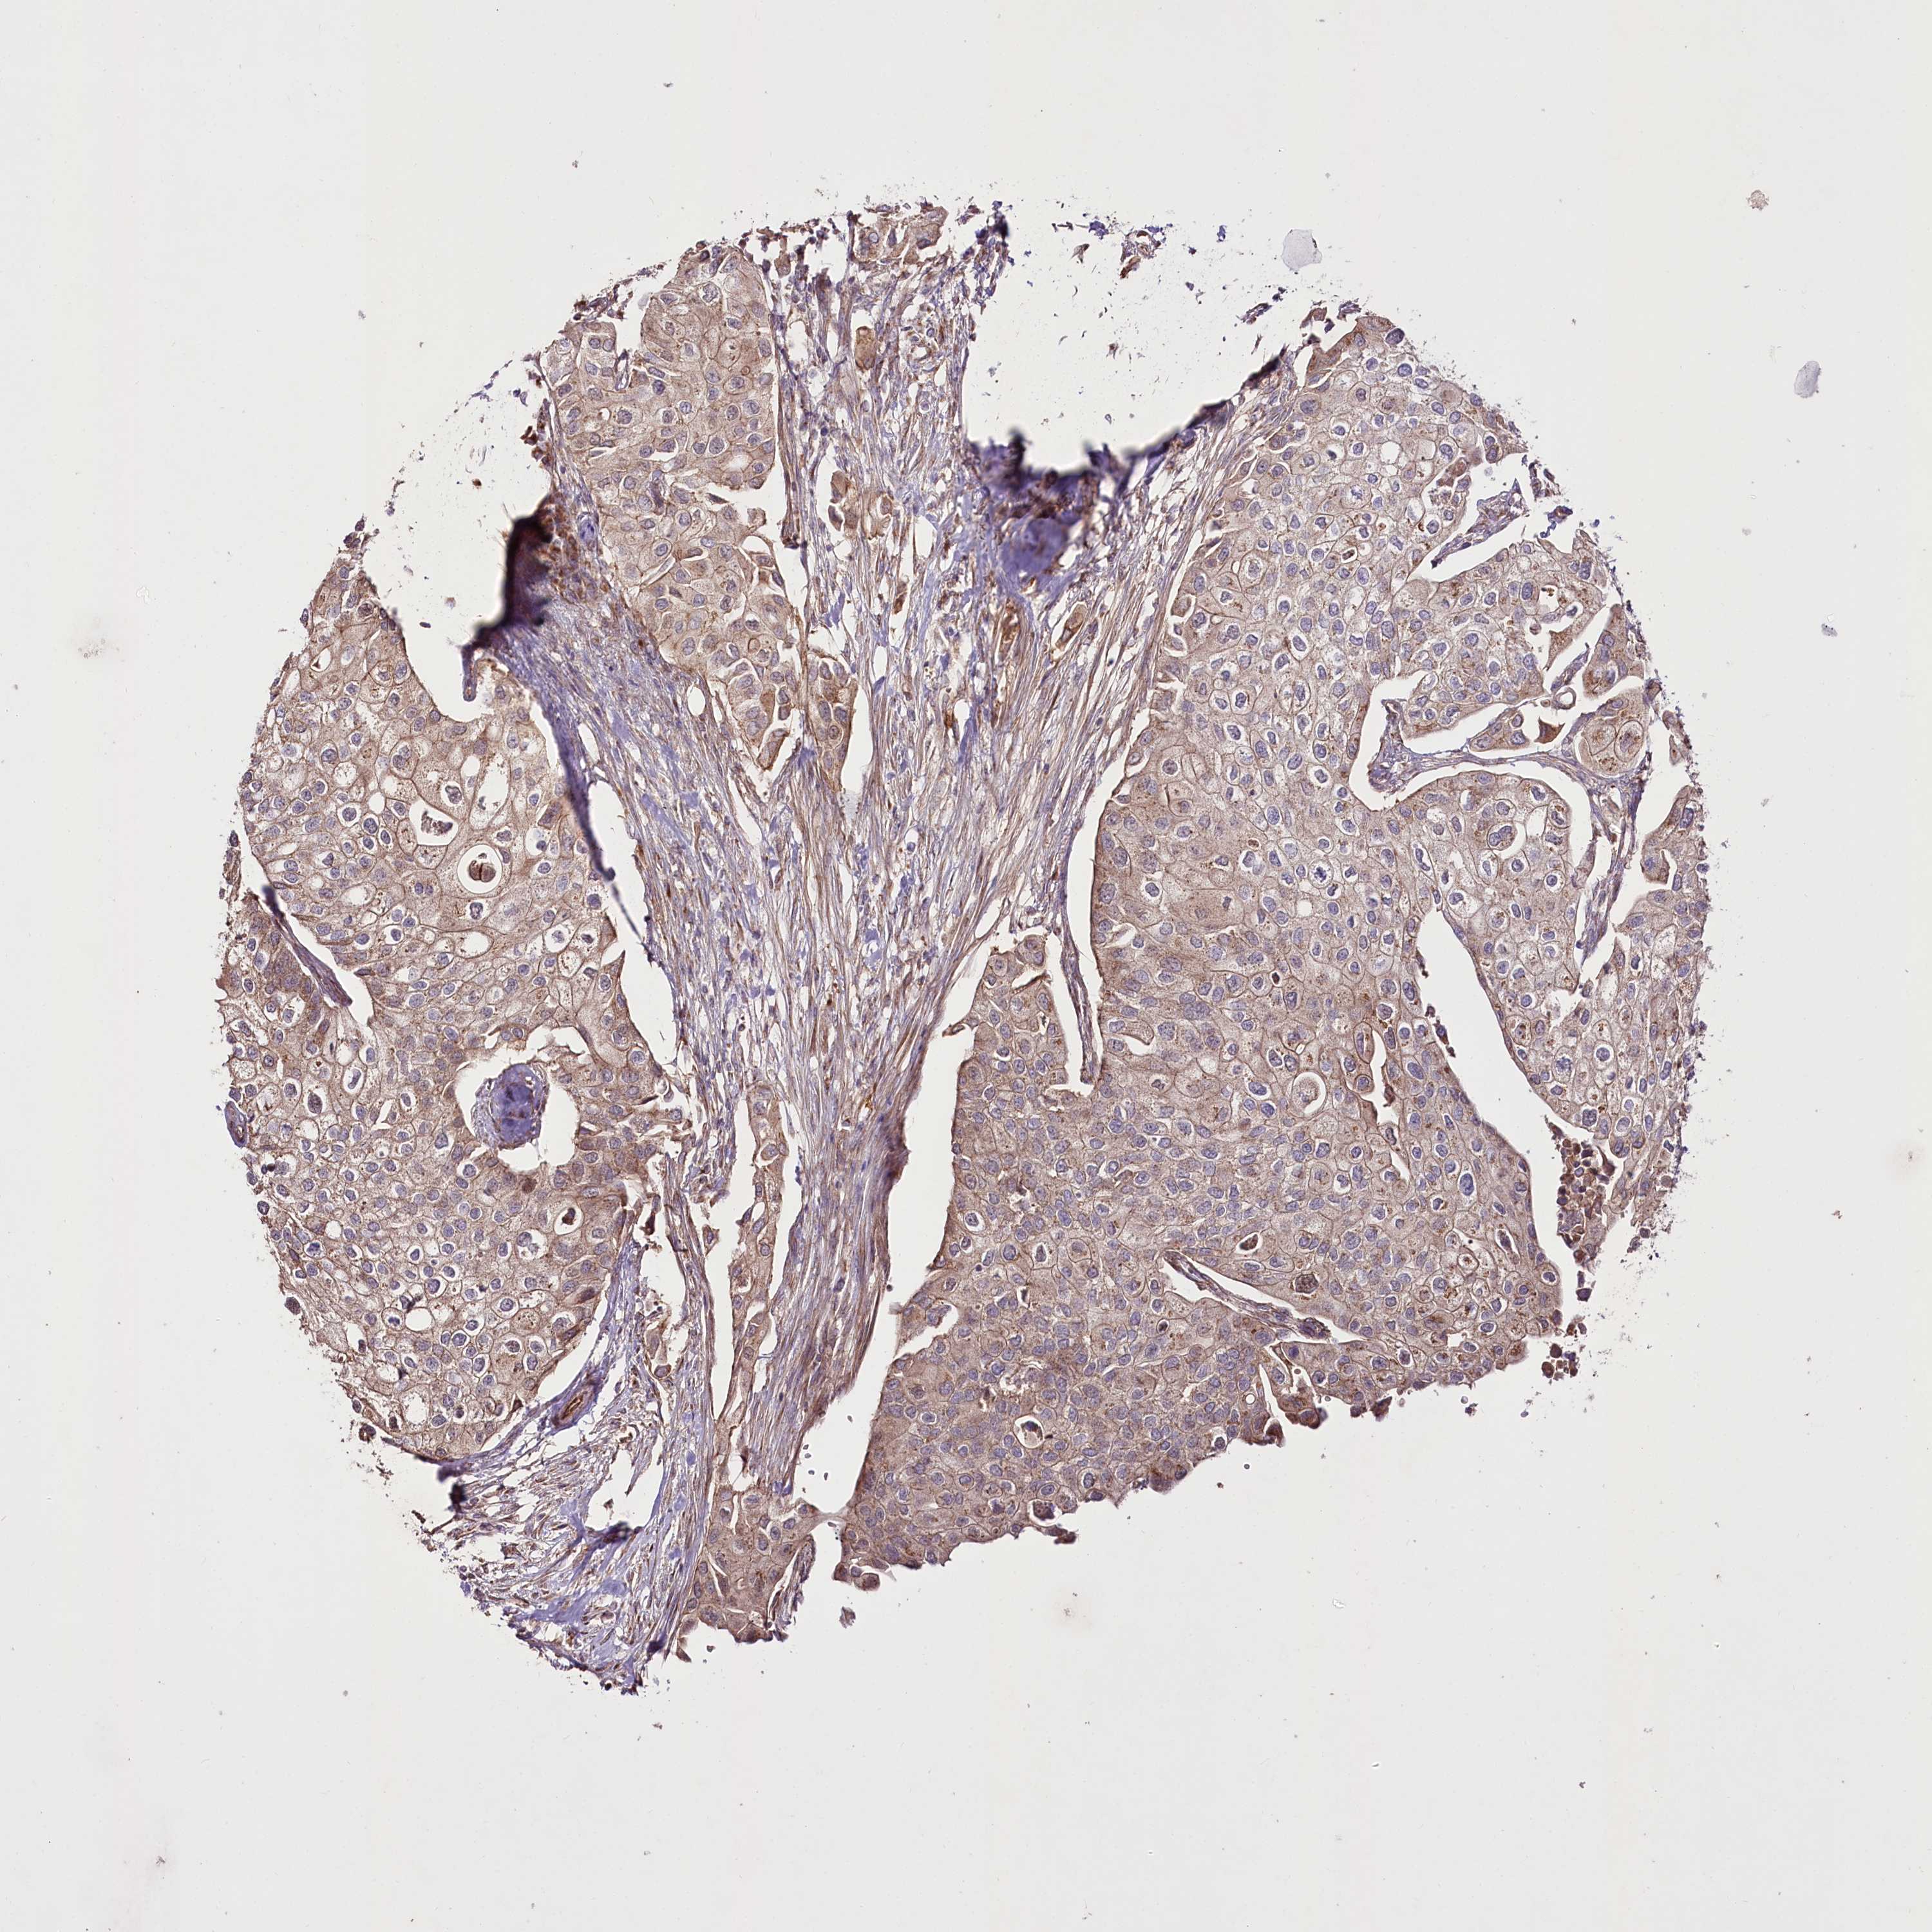

UROTHELIAL CANCER - Protein expressioni

A mouse-over function shows sample information and annotation data. Click on an image to view it in a full screen mode. Samples can be filtered based on level of antibody staining by selecting one or several of the following categories: high, medium, low and not detected. The assay and annotation is described here.

Antibody stainingi

Antibody staining in the annotated cell types in the current human tissue is reported as not detected, low, medium, or high, based on conventional immunohistochemistry profiling in selected tissues. This score is based on the combination of the staining intensity and fraction of stained cells.

Each image is clickable and will lead to virtual microscopy that enables deeper exploration of all samples and also displays staining intensity scores, fraction scores and subcellular localization as well as patient and tissue information for each sample.

Antibody HPA038450

Antibody HPA038451

Staining

High

Medium

Low

Not detected

Intensity

Strong

Moderate

Weak

Negative

Quantity

>75%

75%-25%

<25%

None

Location

Nuclear

Cytoplasmic/membranous

Cytoplasmic/membranous,nuclear

Urothelial carcinoma, High grade

Urothelial carcinoma, Low grade

Urothelial carcinoma, NOS